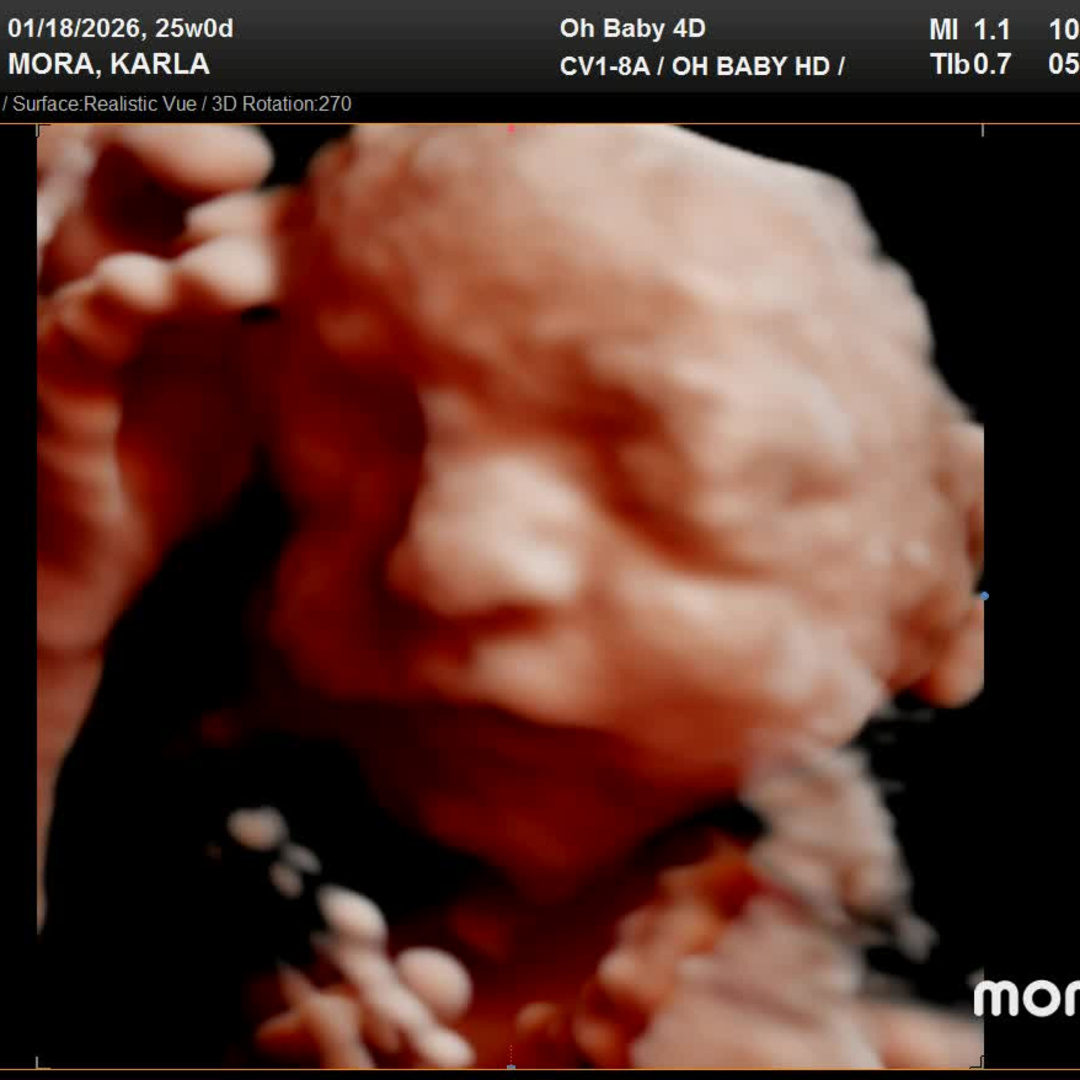

Thank you so much for celebrating baby Mateo with us! We feel incredibly grateful to be surrounded by family and friends who are excited to welcome him into the world. As we prepare for his arrival, we’ve put together a registry with items we thoughtfully chose to help us get started. If you feel moved to give a gift, we would truly appreciate you taking a look there. Your love and support mean more than words.